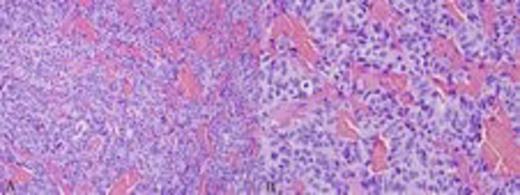

The patient underwent transsphenoidal resection of the pituitary mass to decompress his chiasm and obtain pathology. H&E staining demonstrated a neuroendocrine neoplasm (Fig. 2) with 4 mitotic figures per 10 high-power fields and no necrosis. The tumor appeared to be growing in the vicinity of the pituitary as evidenced by a small portion of Rathke’s cleft epithelium. Based on the morphologic appearance, the main differential included pituitary adenoma versus metastatic carcinoid tumor. Immunohistochemical stains (Fig. 3) showed tumor cells negative for prolactin, adrenocorticotropic hormone, human growth hormone, luteinizing hormone, follicle-stimulating hormone, and thyroid-stimulating hormone. Based on these results, the tumor was diagnosed as a metastatic carcinoid tumor originating from lung primary.

The tumor was growing in a trabecular pattern (a, 200X), including mildly pleomorphic neuroendocrine cells with abundant cytoplasm (b, 400X)